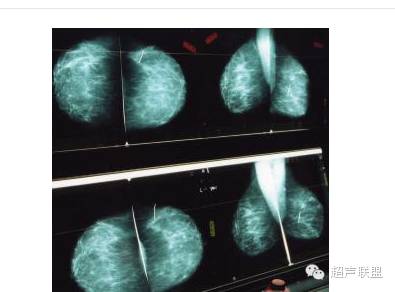

早期癌病人无任何不适,仅在内有一个比较小的肿块,不痛、不疼,也无变化,大多是在医生作体格检查时发现,少数是由病人无意中自行摸到后再请医生确诊。因此,为了早期发现癌,特别是中年妇女应经常自己检查内有无肿块存在。正确的检查方法是将手指伸直并拢进行扪摸,而不是手指抓提,以免将正常的乳腺组织误认为是肿块,如发现内有可疑的肿块,必须请医生检查,并作必要的化验,包括钼靶X线摄片、活体组织切片检查,以明确诊断。

由于早期癌的肿块较小,如不提高警惕,容易被病人忽略,肿块就逐渐增大,侵入周围皮肤或肌肉,与之粘连固定;内缩、抬高,有时有血性液体溢出,这是癌肿浸入大的乳腺导管所致;皮肤是橘皮样变,腋窝淋巴结肿大,质坚硬。晚期癌肿块直径超过5厘米,甚至溃烂,不仅腋窝淋巴结肿大,锁骨上淋巴结、胸骨旁淋巴结 和对侧液窝淋巴结也可肿大。癌细胞也可通过血液转移到肺、骨或肝脏。癌在妊娠期发展特别迅 速,癌肿呈现炎症性,红肿充血、发热、犹如急性乳腺炎,容易误诊,也说明癌的发病与性激素的变化有关。至于癌发病与生育和哺乳究竟有何关系,目前意见尚不一致。癌在肿块中占的比例最大,而且良性肿块也有恶变可能,因此,对妇女肿块应提高警惕,仔细检查,以防误诊、漏诊。癌应与小叶增生病和纤维腺瘤相鉴别。